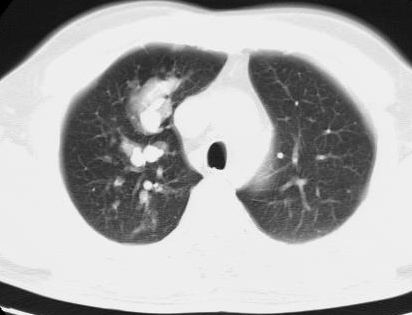

标题: CT15869:男性,71岁,因咳嗽而就诊,请讨论右上肺病变性质 [打印本页]

患者,男性,71岁,因咳嗽而就诊,

右肺门淋巴结结核可能性大

典型的右肺中心性肺癌并纵隔淋巴结转移

右肺中心性肺癌并纵隔淋巴结转移可能性大!

病灶中等程度强化 还是支持肺癌诊断